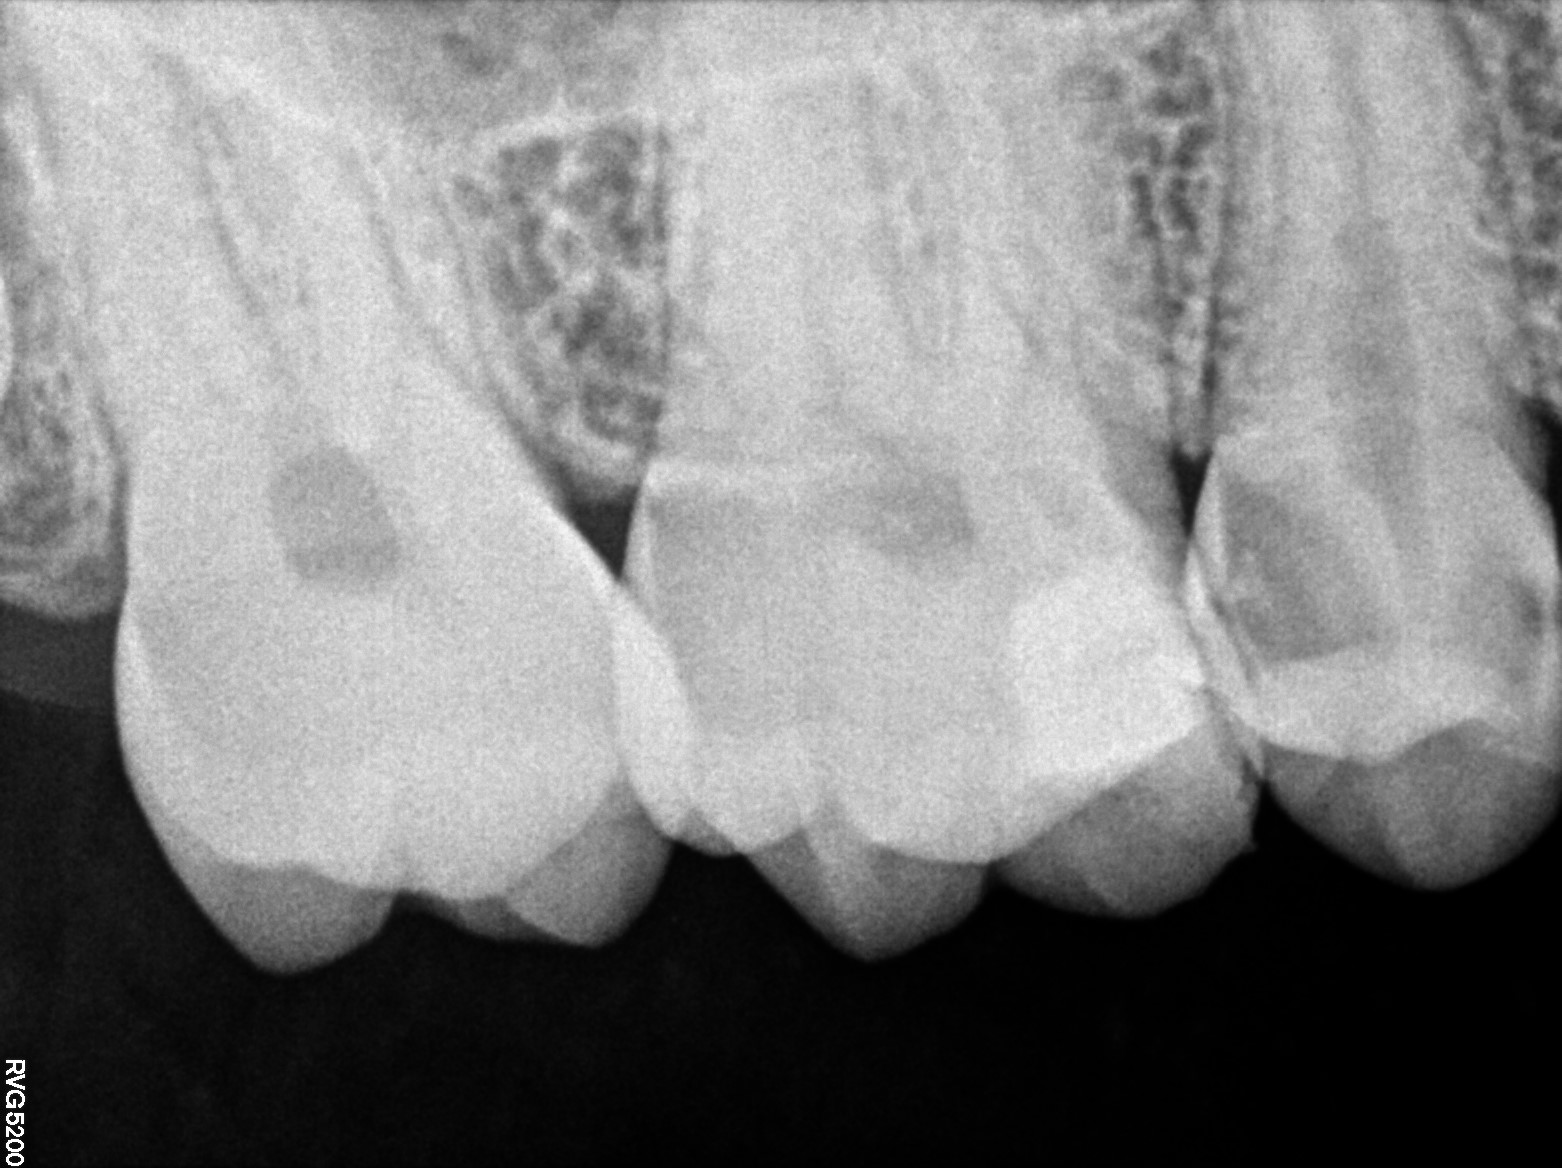

Dental Radiographs FHIR: DocumentReference · LOINC 24641-7

R53.jpg

24641-7